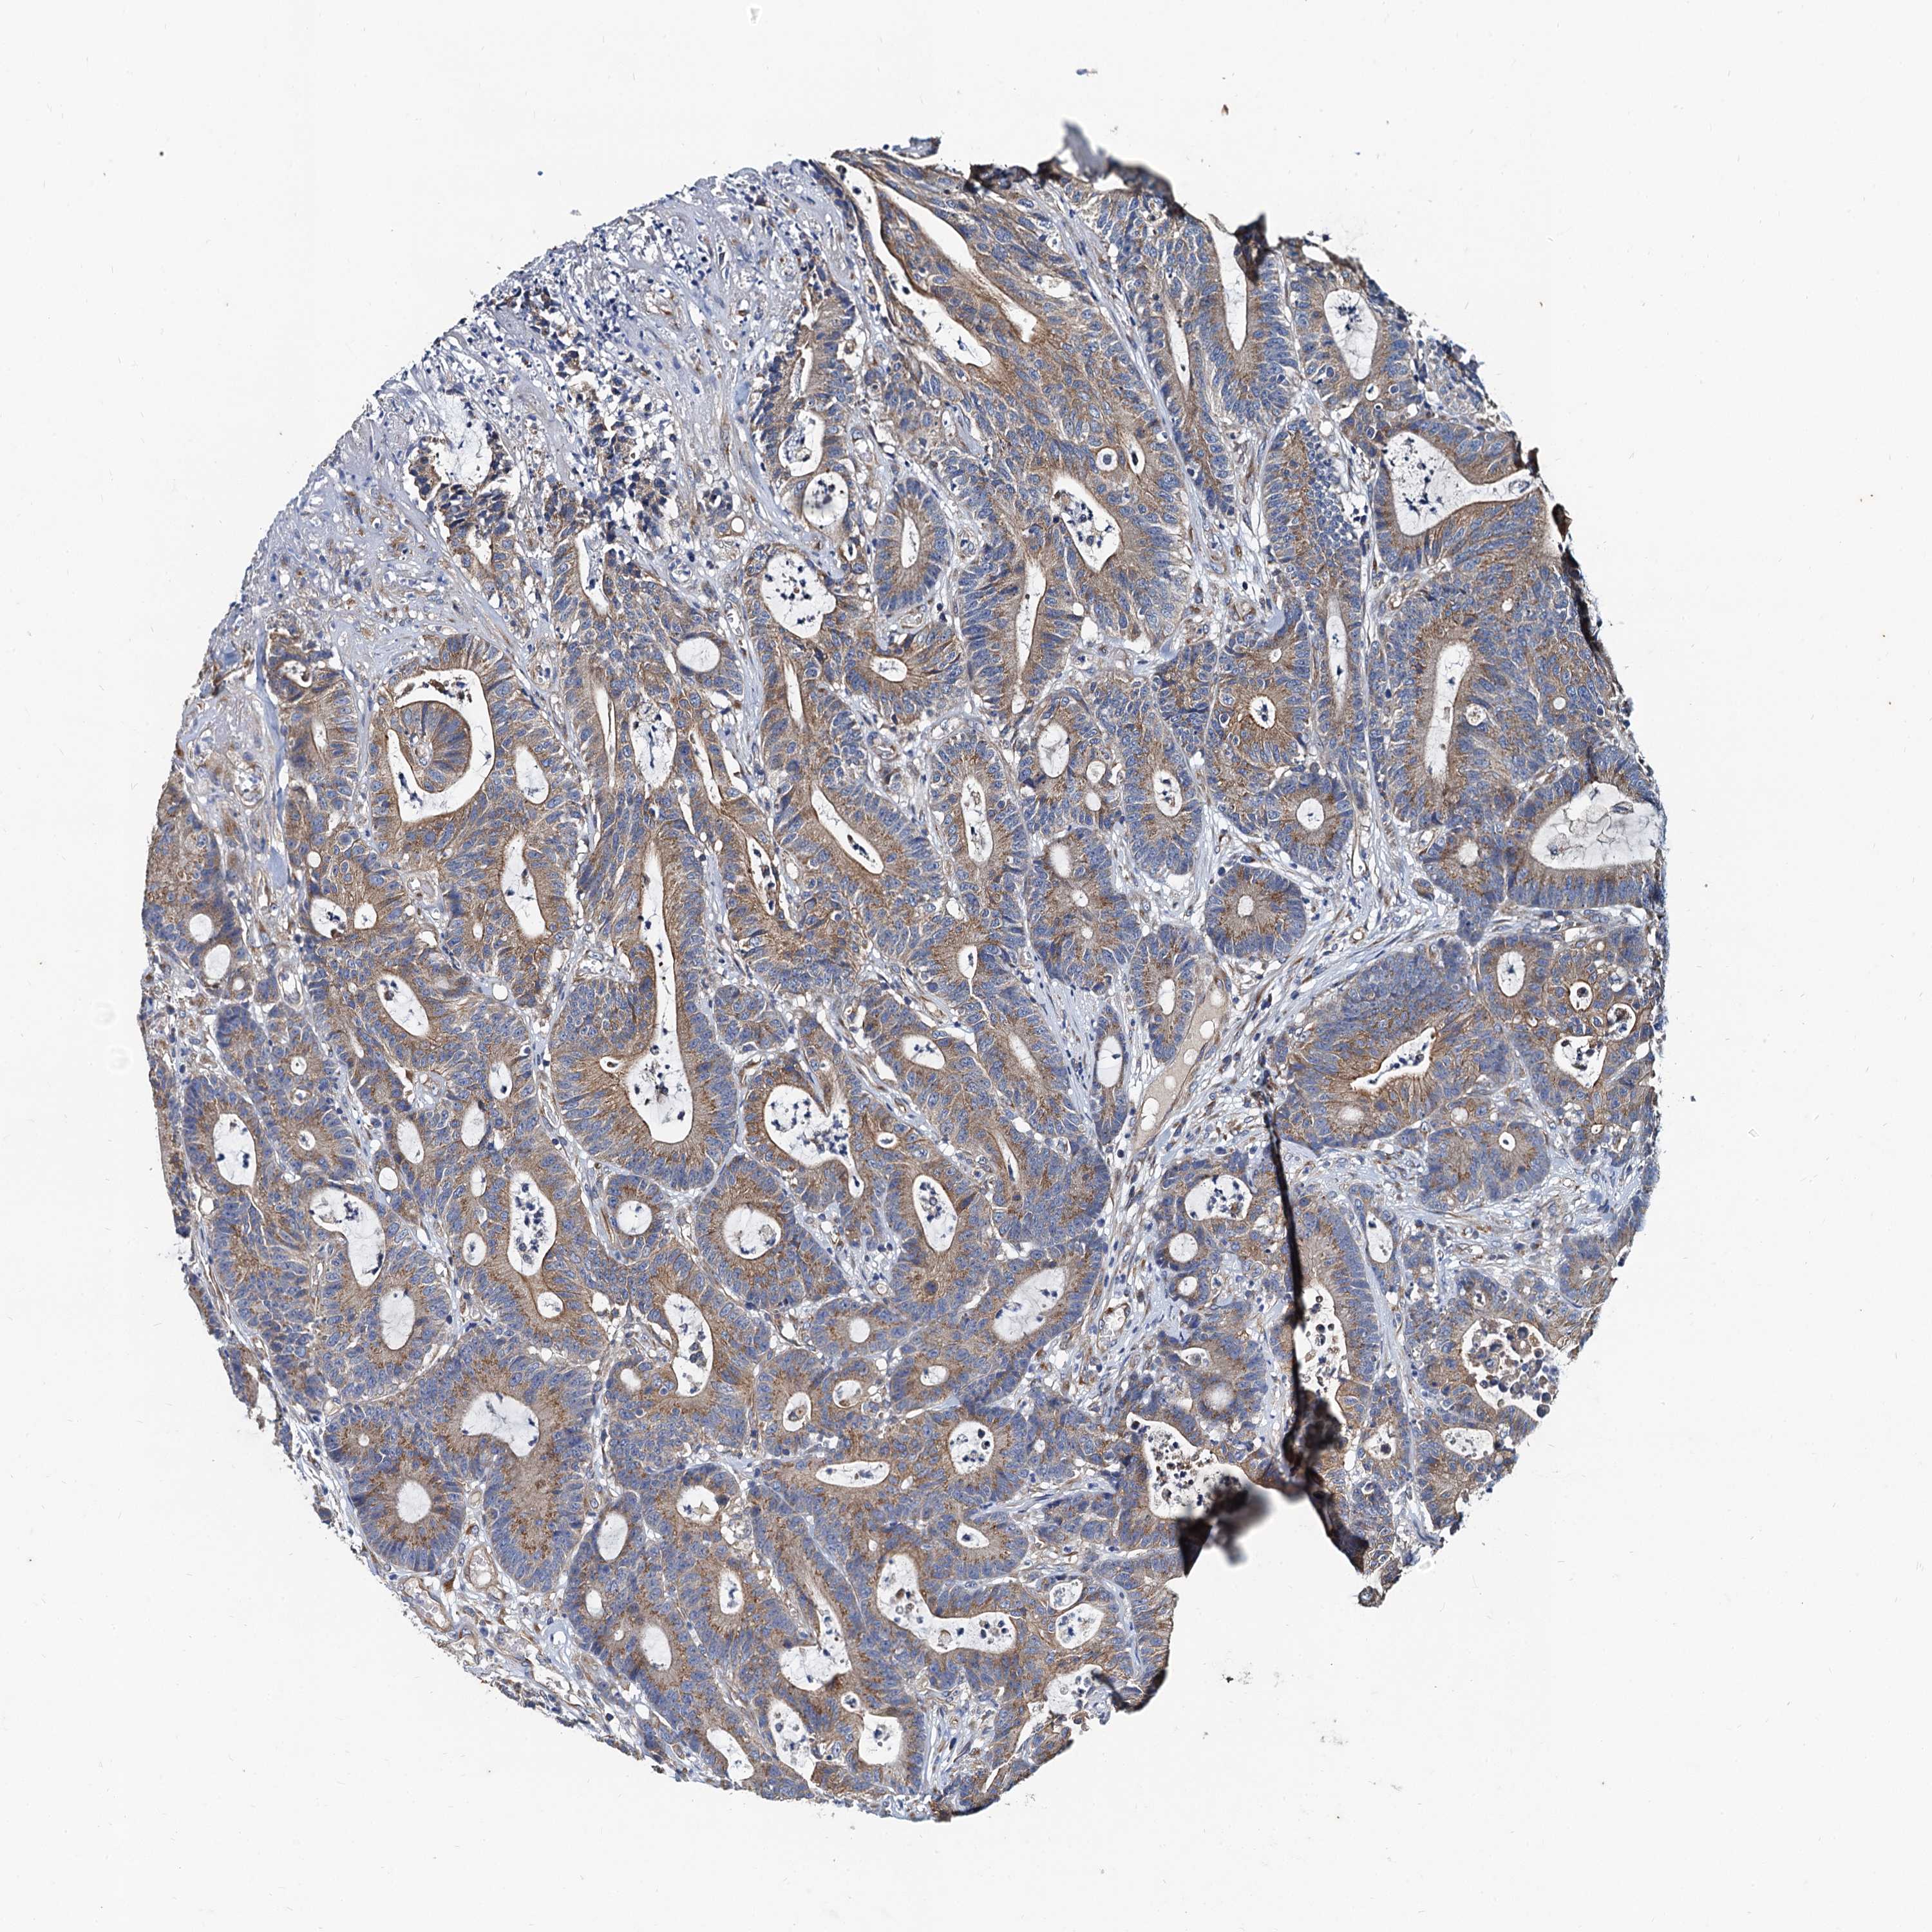

CANCER COLORECTAL CANCER Show tissue menu

COAD TCGA COAD VALIDATION READ TCGA READ VALIDATION PROTEIN COAD CPTAC PROTEIN EXPRESSION

ANTIBODIES

AND

VALIDATION